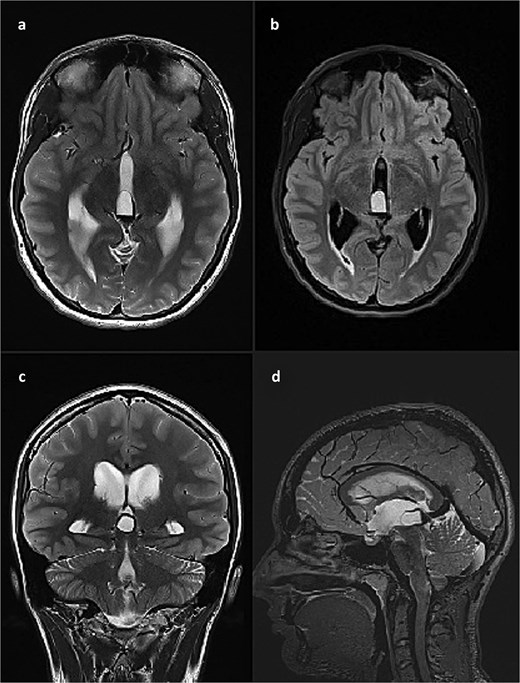

This finding was in concordance with a brain magnetic resonance imaging (MRI) done the previous day in another hospital which described hemosiderin deposits within the dorsal part of the cyst, with complete interruption of the cerebrospinal fluid (CSF) communication at the level of mesencephalic aqueduct, and a 4 mm long cerebral tonsil protrusion (Fig. 2).

Brain MRI scan. (a) T2 weighted image, axial slice, pineal cyst occupying posterior part of the third ventricle with hemosiderin deposits in the posterior part of the cyst; (b) FLAIR image, axial slice, showing different contents inside the cyst when compared to CSF; (c) T2 weighted image, coronal slice, pineal cyst inside the lower part of the third ventricle, beneath internal cerebral veins; (d) T2 weighted image (SPACE), sagittal slice, showing pineal cyst in front of a rather large vein of Galeni, and compressing the cranial part of the cerebral aqueduct.